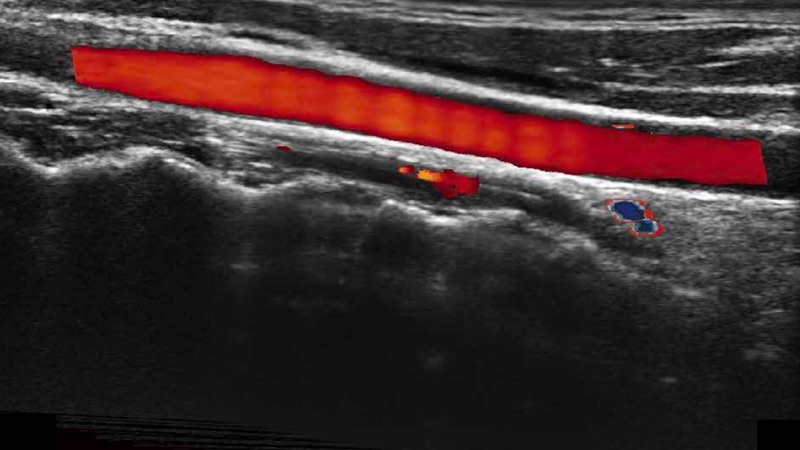

高分辨率血流成像技術(shù)提高了對(duì)低速血流信號(hào)的檢測(cè)能力。在提高空間分辨率的同時(shí),也克服了血流外溢現(xiàn)象,為用戶提供更加真實(shí)的血流動(dòng)力學(xué)信息。

凸陣、線陣和相控陣探頭進(jìn)行實(shí)時(shí)掃描時(shí),開(kāi)啟擴(kuò)展成像模式,可以擴(kuò)展超聲圖像視野,以便更完整地查看大的病灶或組織器官的解剖結(jié)構(gòu)。

通過(guò)色彩血流和實(shí)時(shí)寬景相結(jié)合,可觀察到完整的靜脈或動(dòng)脈的血流,方便醫(yī)生檢查。實(shí)時(shí)掃查過(guò)程中,如有任何操作失誤也可以很容易地進(jìn)行回掃擦除,而不會(huì)中斷掃查。